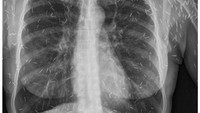

Foto X-ray remaja berusia 17 tahun di Kanada yang mengalami kondisi langka 'popcorn lung' akibat kebiasaan menghisap vape. (Foto: Canadian Medical Association Journal)

Foto X-ray remaja berusia 17 tahun di Kanada yang mengalami kondisi langka popcorn lung akibat kebiasaan menghisap vape. (Foto: Canadian Medical Association Journal)